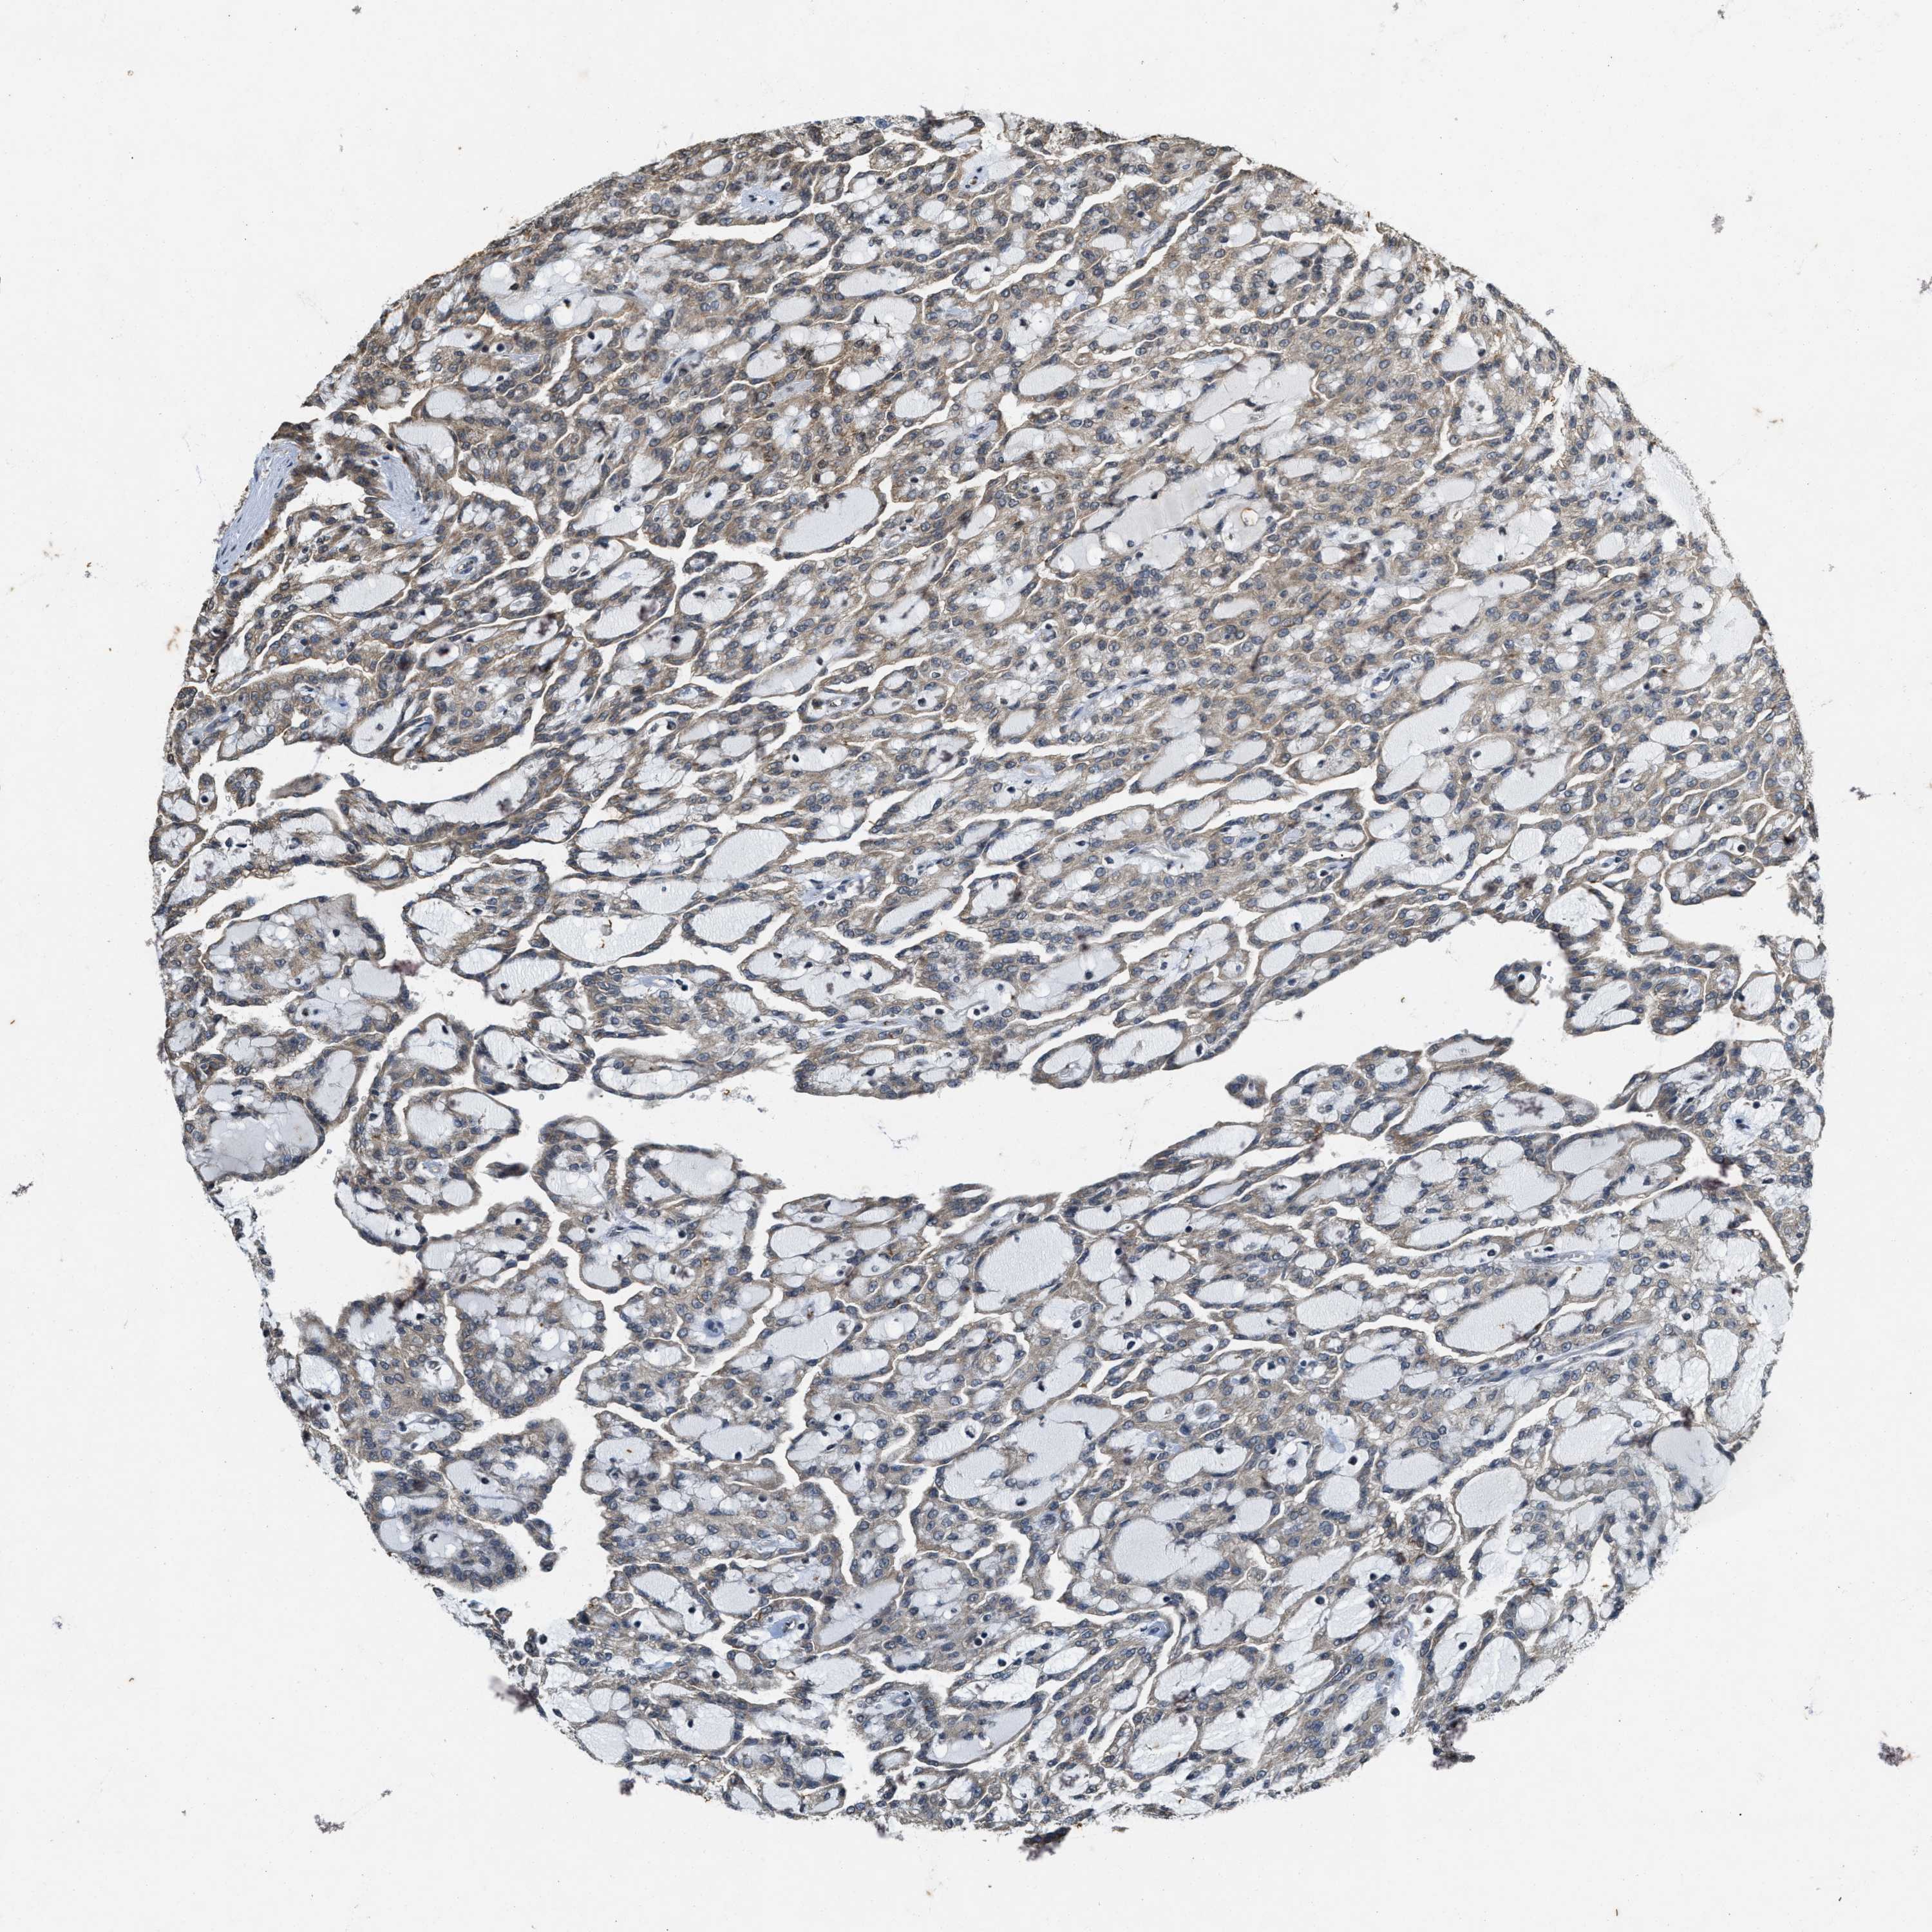

KIDNEY RENAL CLEAR CELL CARCINOMA (VALIDATION) - Interactive survival scatter ploti

The Survival Scatter plot shows the clinical status (i.e. dead or alive) for all individuals in the patient cohort, based on the same data that underlies the corresponding Kaplan-Meier plots. Patients that are alive at last time for follow-up are shown in blue and patients who have died during the study are shown in red.

The x-axis shows the expression levels (FPKM) of the investigated gene in the tumor tissue at the time of diagnosis. The y-axis shows the follow-up time after diagnosis (years). Both axes are complimented with kernel density curves demonstrating the data density over the axes. The top density plot shows the expression levels (FPKM) distribution among dead (red) and alive patients (blue). The right density plot shows the data density of the survived years of dead patients with high and low expression levels respectively, stratified using the cutoff indicated by the vertical dashed line through the Survival Scatter plot. This cutoff is automatically defined based on the FPKM cutoff that minimizes the p-score. The cutoff can be changed by dragging the vertical line or by entering a cutoff value in the square labeled "Current cut-off".

Under the Survival Scatter plot the p-score landscape (black curve; left axis) is shown together with dead median separation (red curve; right axis). Dead median separation is the difference in median mRNA expression between patients who have died with high and low expression, respectively. It is calculated as follows: median FPKM expression of dead patients with high expression - median FPKM expression of dead patients with low expression. This is intended to aid the user in visually exploring custom cutoffs and the associated p-scores and dead median separation.

Individual patient data is displayed and can be filtered by clicking on one or more of the category buttons on the top of the page. Categories describing expression level and patient information include: high, low, alive, dead, female, male and tumor stages. The scale of the x-axis can be toggled between linear and log-scale by clicking on the "x log" button. Mouse-over function shows TCGA ID, patient information and mRNA expression (FPKM) for each patient.

& Survival analysisi

Kaplan-Meier plots summarize results from analysis of correlation between mRNA expression level and patient survival. Patients were divided based on level of expression into one of the two groups "low" (under cut off) or "high" (over cut off). X-axis shows time for survival (years) and y-axis shows the probability of survival, where 1.0 corresponds to 100 percent.

KIF21A is not prognostic in Kidney Renal Clear Cell Carcinoma (validation)

Best expression cut offi

: 23.65

P scorei

N/A

Average pTPM 27.2

Number of samples 100